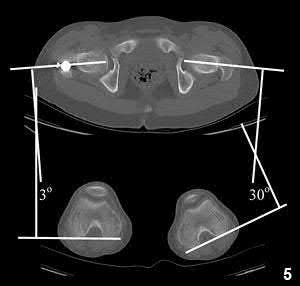

Question 13:

During a total knee arthroplasty (TKA), the surgeon aims to optimize patellofemoral tracking. Which of the following femoral component positioning errors is most likely to cause patellar maltracking and lateral subluxation?

Correct Answer: Internal rotation of the femoral component

Explanation:

Internal rotation of the femoral component effectively moves the trochlear groove medially relative to the mechanical axis. This increases the Q-angle, leading to lateral patellar maltracking and a higher risk of lateral patellar subluxation or dislocation.